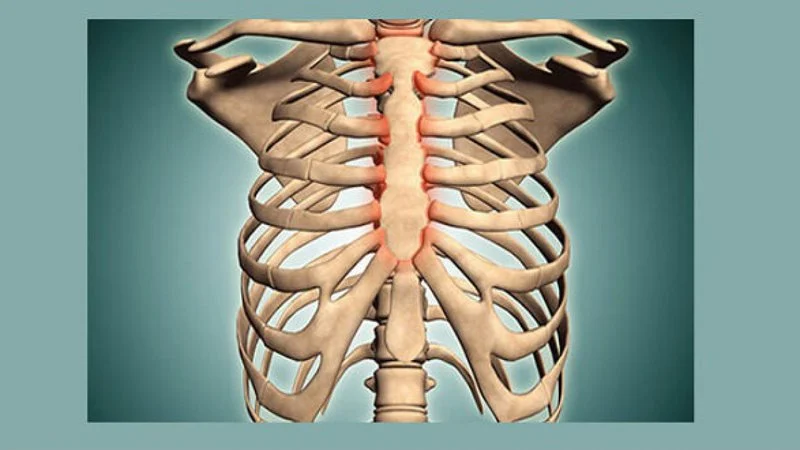

Tổn thương này có thể xuất hiện ở bất kỳ xương nào, nhưng thường được tìm thấy trong tủy và chủ yếu là ở các xương dài gần với vùng sụn phát triển. Các vị trí phổ biến bao gồm xương cánh tay (50 - 60% trường hợp), đầu xương đùi (khoảng 30%), và các xương dài khác, cũng như xương bàn chân.

Ở người lớn, u nang xương đơn độc cũng có thể xuất hiện ở xương chậu (2% trường hợp) và xương cột sống. Ngược lại, ở trẻ em, xương cánh chậu và các xương nhỏ cũng là những vị trí thường gặp.